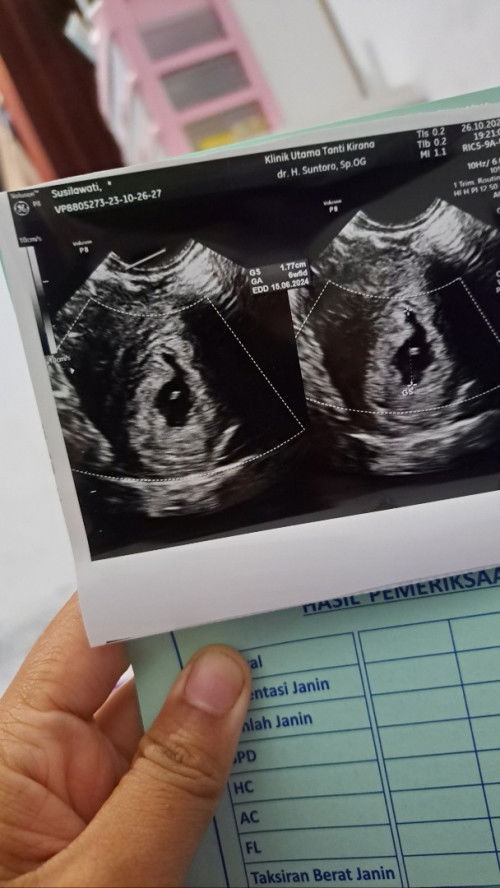

Bun mau tanyaa, janin ku tidak berkembang semenjak usia 6week sedngkan sekarang sudah memasuki usia 9 week, namun jika bener tidak berkembang kenapa ya dia tidak dgn sendiri nya keluar si jaringan nya, dok nyaranin kuret, tapi aku belum siap, dn banyak nyaranin nunggu keluar alami baru minta obat untuk pembersihan, mohon bagi pengalaman nya barangkali ada yg pernah..apa boleh nunggu sampe bener pendarahan, soalnya sampe sekrng tidk ada pendarahan, hanya flek dn itu pun sudah berhentii#seriusnanya #bantusharing #pleasehelp #firstmom #firstbaby